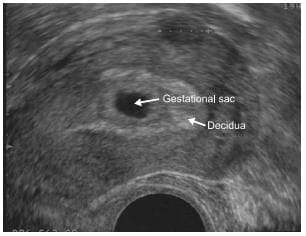

Differential diagnosis between early intrauterine gestational sac and Pseudosac

A longitudinal section through the uterus showing a normal early intrauterine pregnancy at 5 weeks' gestation. The sac is surrounded by a well-defined layer of trophoblast tissue and thick decidua.